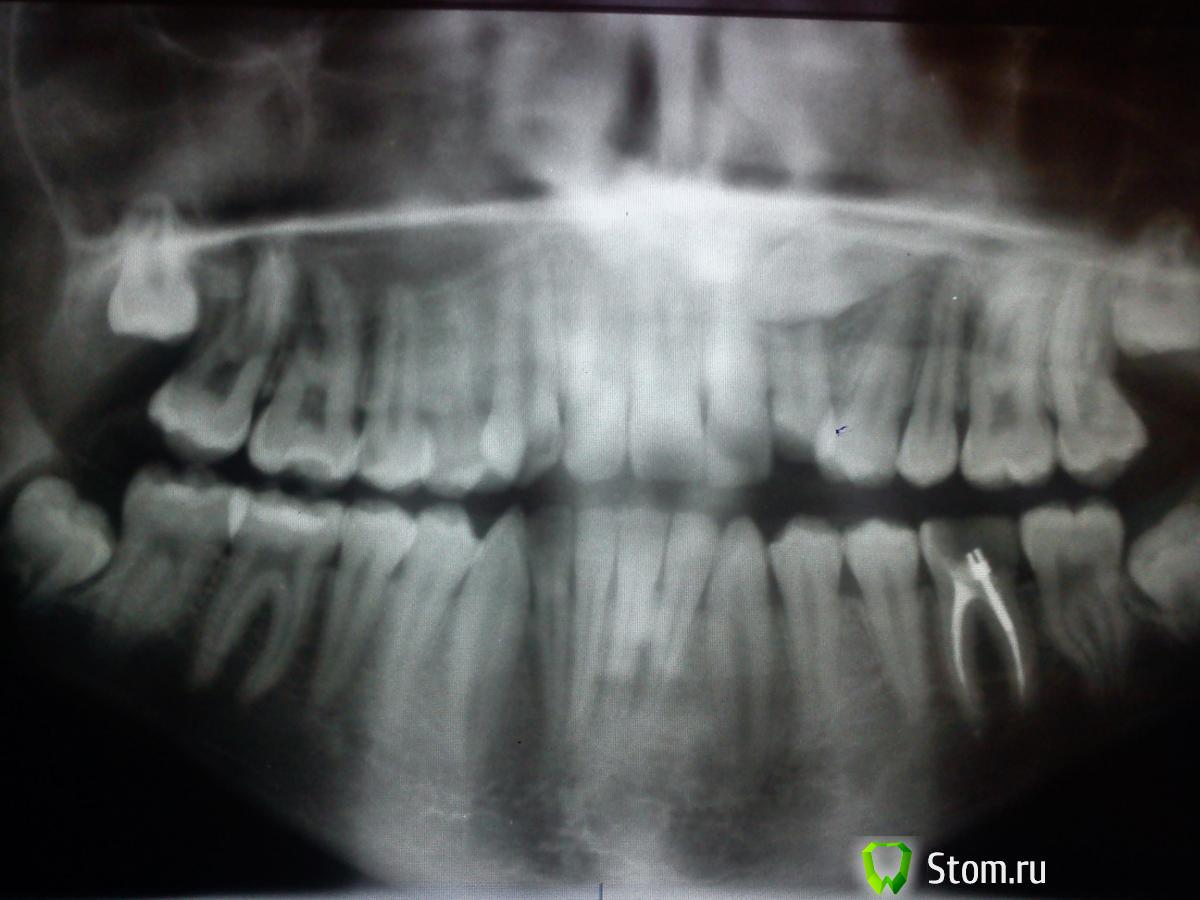

Здравствуйте, хотелось бы узнать ваше мнение по моему случаю, у нас в городе всего 2 ортодонта, поэтому не с кем сравнивать мнения...Возможно ли вытянуть верхний клык(находится чуть правее середины верхней челюсти если что)? и высока ли вероятность успешного вытягивания? и в итоге челюсть верхняя станет нормальной, шире т.е.?post-27116-0-06863100-1331627193_thumb.jpgpost-27116-0-84361200-1331627177_thumb.jpg